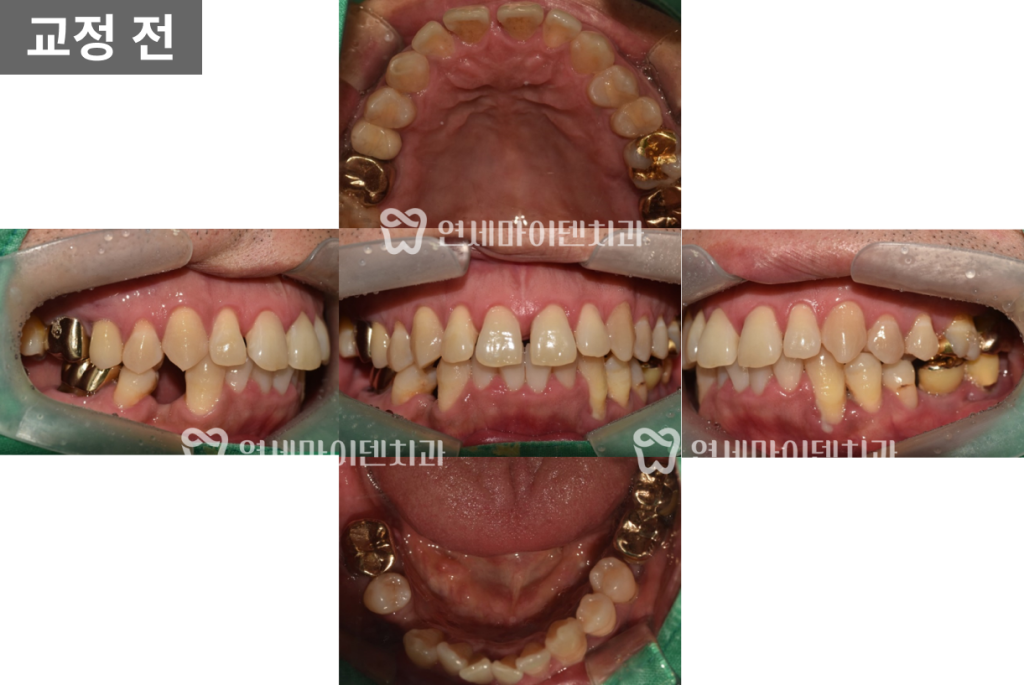

초진 시 구강 내 사진을 보면

아랫니가 안쪽으로 많이 쓰러져 있었습니다.

또, 앞니 사이도 많이 벌어져 있어서

심미적으로 좋지 않은 모습이었습니다.

게다가 아래 송곳니 주변의 잇몸은 많이 내려가 있고,

잇몸 염증까지 보이는 상황이라서

치아 교정이나 수복을 바로 시작하기에는

여러가지 제약이 있었습니다.